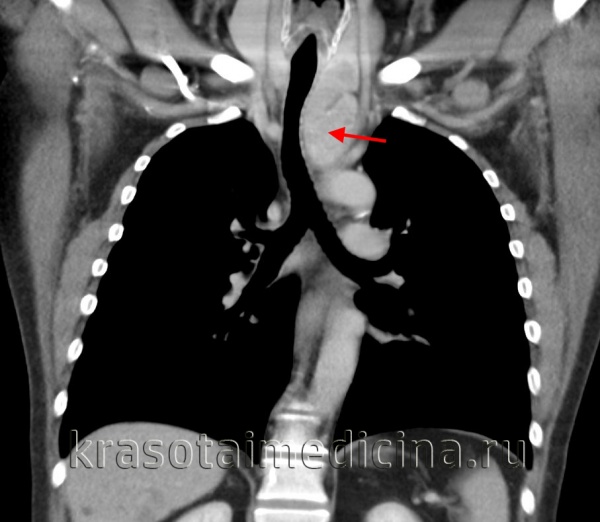

КТ ОГК. Массивное объемное образование верхнего средостения с объемным воздействием на трахею, исходящее из щитовидной железы.